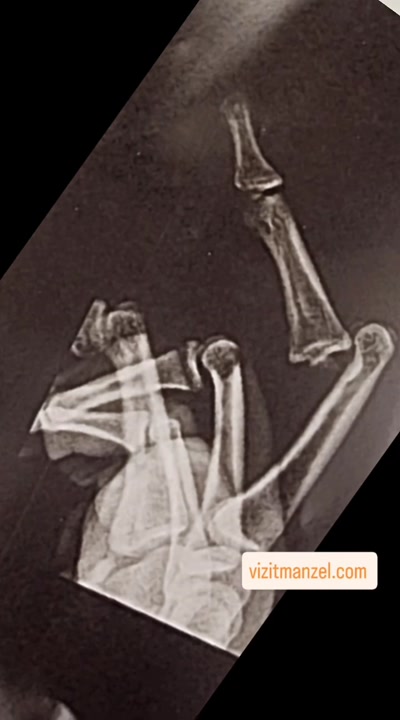

درمان شکستگی انگشت